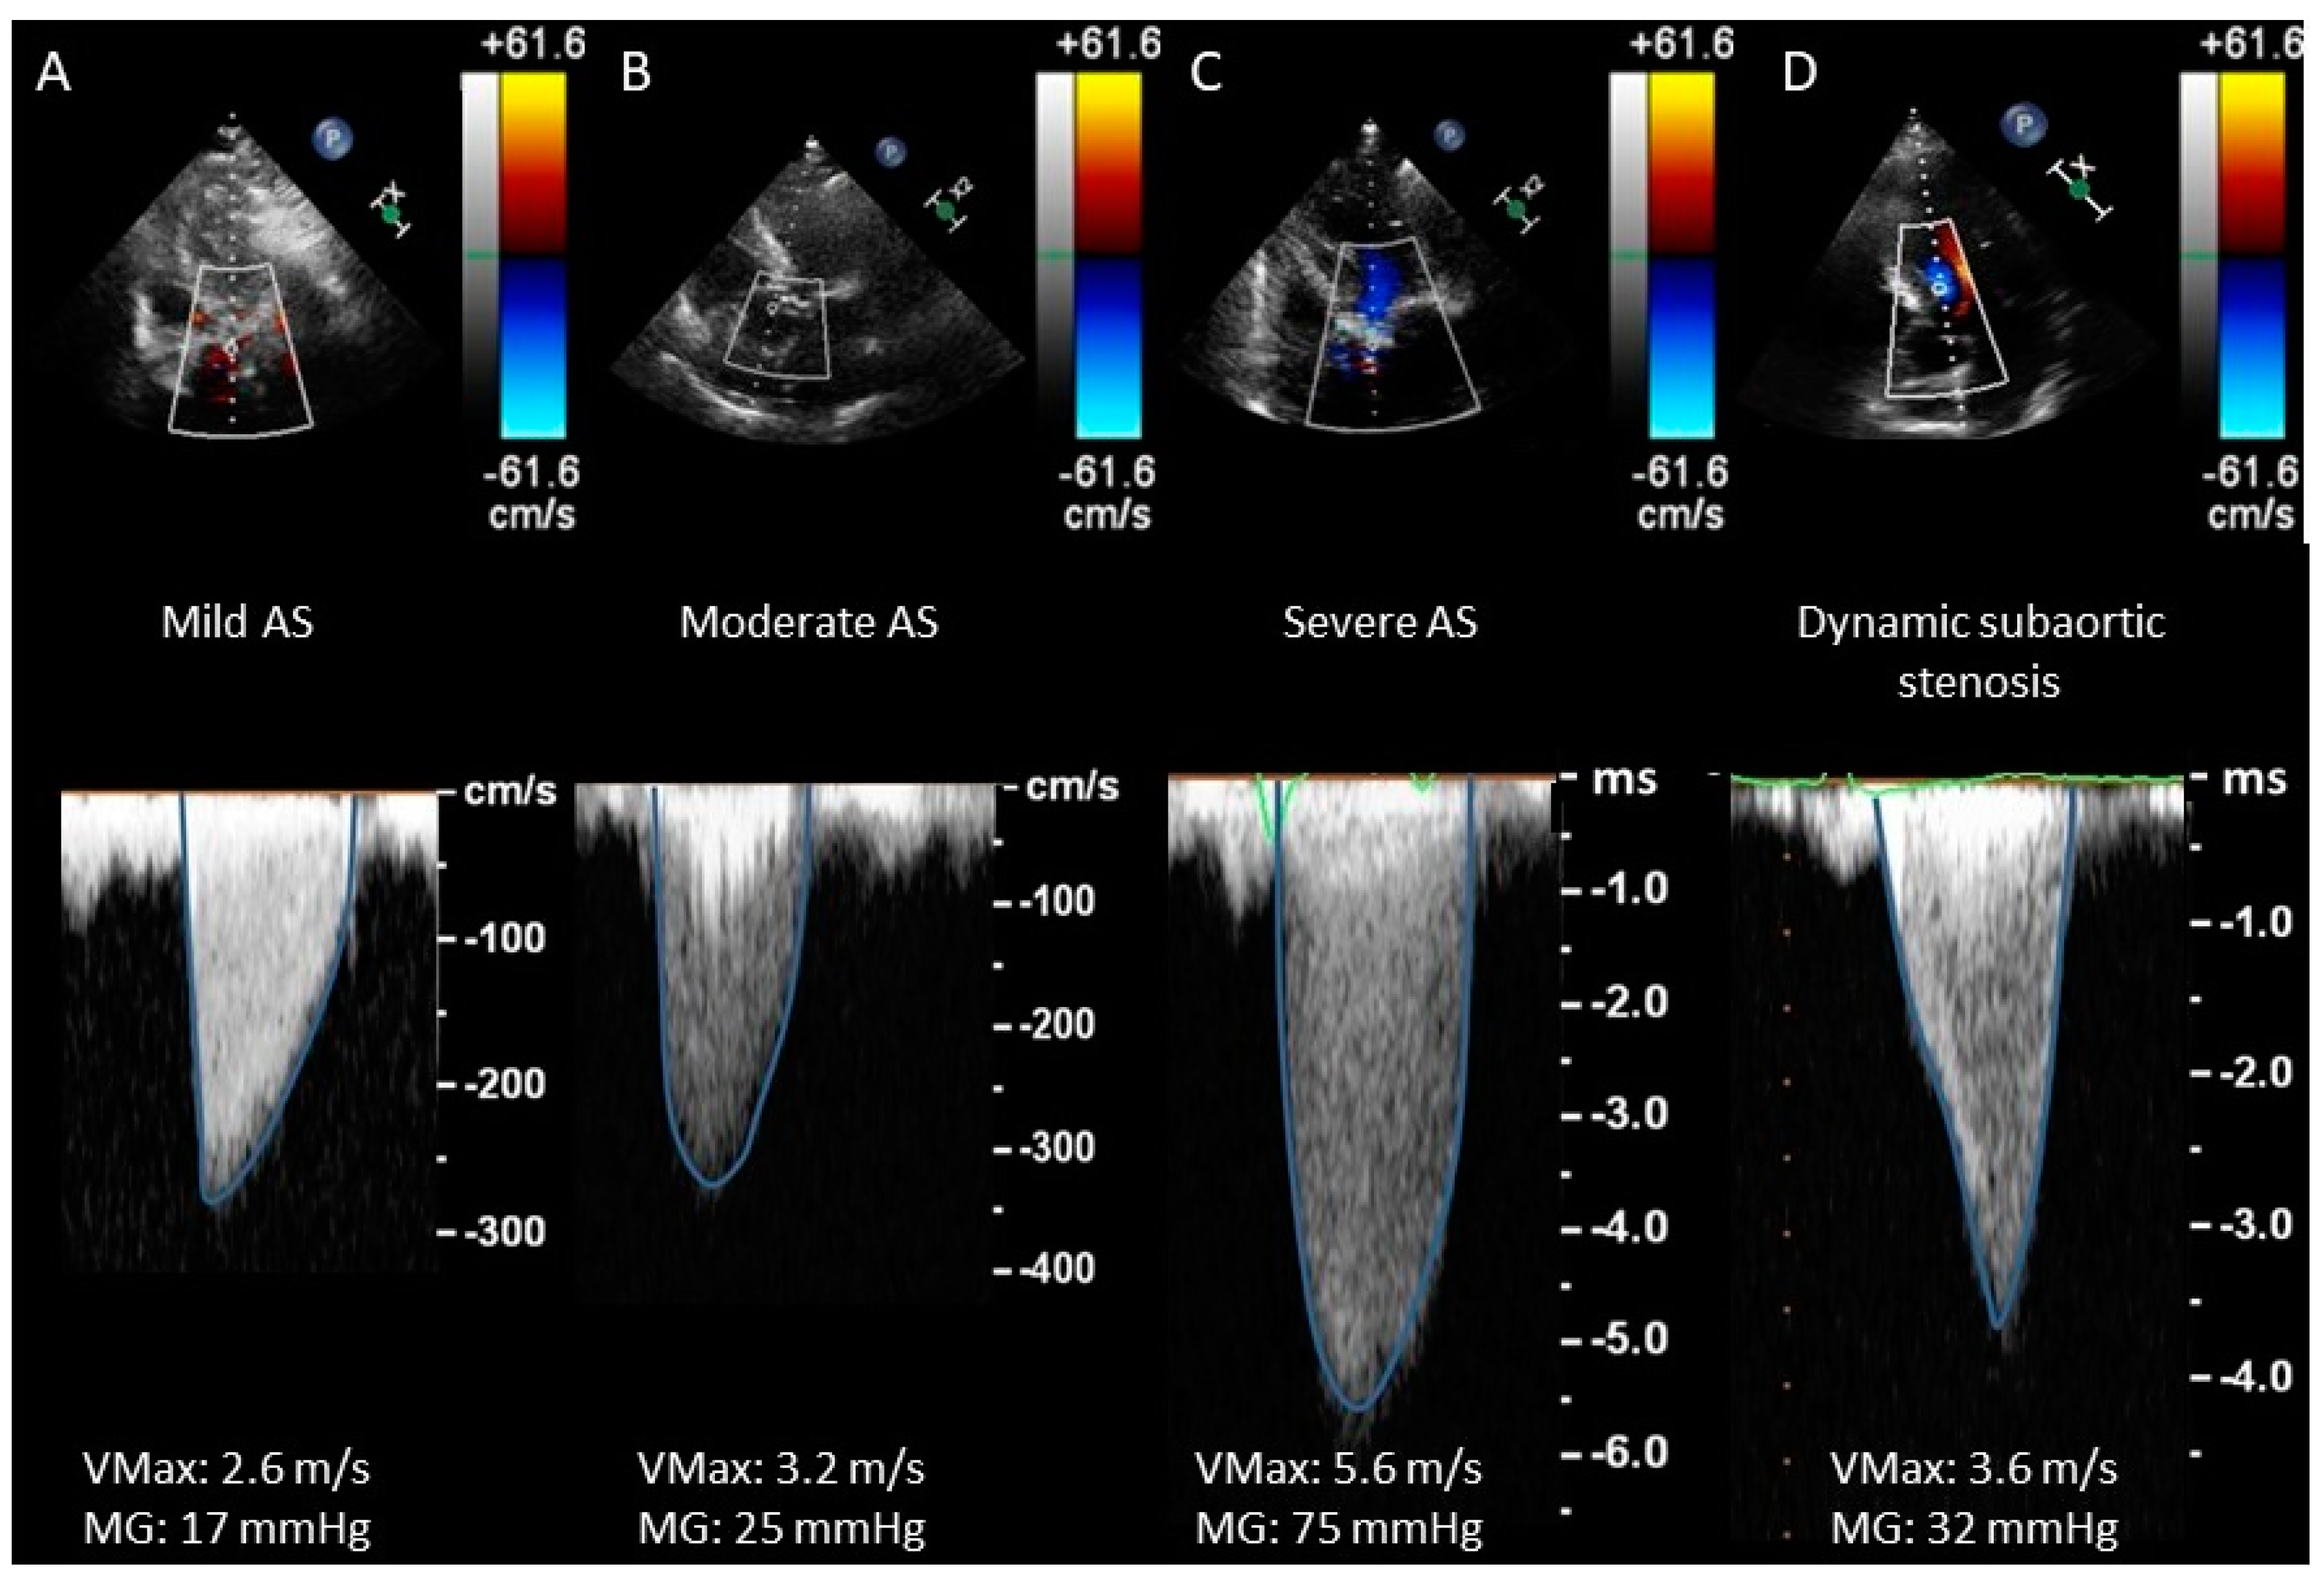

- Assessment of transvalvular flow velocity by Doppler technique is angle-dependent (see Figure 3).

- The simplified Bernoulli equation can be unsuitable in cases where high LVOT velocities are present (i.e., subaortic membrane or obstructive hypertrophic cardiomyopathy).

- CWD waveform (see Figure 4) is a semiquantitative parameter to evaluate the severity of AS. The finding of a CW waveform with a rapid acceleration and an early peak makes severe AS very unlikely. On the other hand, a slower acceleration with a late peak is more specific to severe AS. A dagger-shaped pattern may correspond to a dynamic subvalvular aortic stenosis (a common feature of obstructive hypertrophic cardiomyopathy) [27].